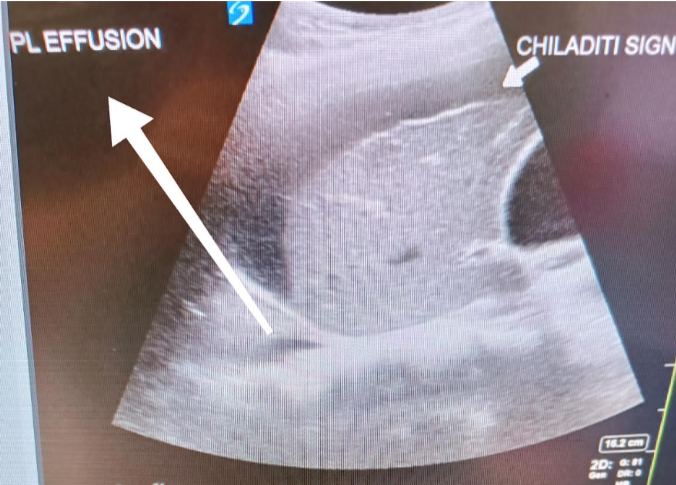

An 80-year-old patient presented with right-sided chest pain, cough, hypoxia requiring supplemental oxygen (1–2 L/min via nasal cannula to maintain SpO₂ >94%), and concurrent right upper abdominal pain, nausea, and vomiting. Point-of-care ultrasound (POCUS) at triage, performed to evaluate the cause of hypoxia, revealed a hypoechoic strip in the subdiaphragmatic region, initially raising suspicion for subphrenic collection. Further scanning demonstrated haustral folds/plicae circularis within the hypoechoic structure, consistent with bowel interposition over the liver. Lung ultrasound revealed right basal consolidation with a small pleural effusion. Chest radiography corroborated the presence of bowel loops between the diaphragm and liver, confirming Chilaiditi sign. Gallbladder assessment showed possible adenomyomatosis, without pericholecystic fluid, shadowing, or mobility with repositioning.

Chilaiditi sign is a rare radiological finding in which bowel loops interpose between the liver and right hemidiaphragm. When associated with clinical symptoms, the condition is termed Chilaiditi syndrome. Its significance lies in its potential to mimic more sinister pathologies such as subphrenic abscess, pneumoperitoneum, bowel obstruction, volvulus, or diaphragmatic hernia, often leading to diagnostic uncertainty in acutely unwell patients.

This case highlights the diagnostic challenge posed by Chilaiditi sign, particularly in symptomatic patients where it constitutes Chilaiditi syndrome. The condition may mimic intra-abdominal abscess, pneumoperitoneum, or bowel pathology, with potential for misinterpretation. Sonographic recognition of haustral/plicae markings is a key feature distinguishing bowel interposition from true subdiaphragmatic collections. Awareness of this entity can prevent unnecessary invasive interventions.